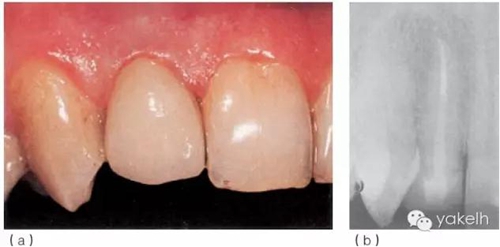

¤¤首先,使用超聲器械清理根管,確保樁道內(nèi)的根管壁上沒有牙膠及根管封閉劑殘留;通過試戴,選擇合適的纖維樁(圖6.3.5a);酒精擦拭樁道后,進(jìn)行酸蝕、沖洗、干燥;使用復(fù)合樹脂粘結(jié)劑粘樁(圖6.3.5b),光固化(圖6.3.5c);在樁及剩余牙體表面涂布牙本質(zhì)粘結(jié)劑,逐層堆塑樹脂核;樹脂核完成后,即刻行冠部預(yù)備(圖6.3.5d);制取印模,使用術(shù)前模型制作丙烯酸臨時(shí)冠;拍攝術(shù)后X線片(圖6.3.5e);2周后復(fù)診,粘固永久性全冠(圖6.3.6a);1年后復(fù)查,患者無不適,根尖X線片顯示患牙根尖周組織正常(圖6.3.6b)。

圖6.3.6(a)粘固永久性全冠。(b)12術(shù)后1年復(fù)查X線片。